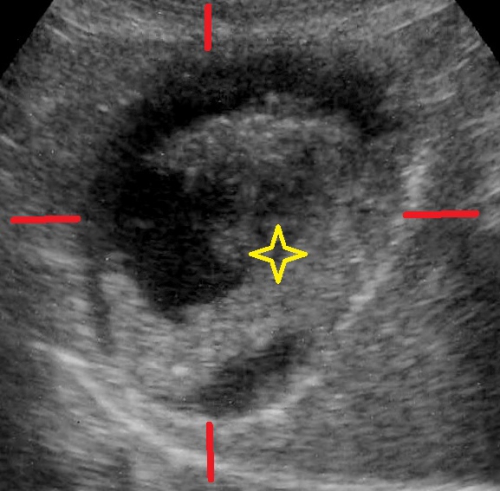

胆泥症の診断は超音波検査によって行われます。典型的な胆泥は画像上で黒く抜けて見える正常な胆汁を背景に胆嚢内を「半月状や不整形」に占拠するような見え方をするのが特徴です。また、また超音波プローブの動きや患者さんの姿勢変化で胆嚢内を緩やかに流動して沈殿するような見え方を特徴とします。

(下図で赤い線に囲まれた黒い円が胆嚢です。胆泥は黄色星印で示しています。)